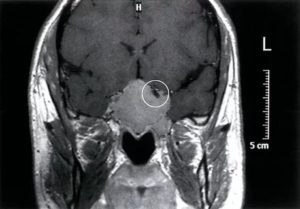

Аденома гипофиза, фото в прямой и боковой проекциях

МРТ гипофиза выявляет также опухоли и кистозные образования, позволяя своевременно приступить к лечению патологии. Аденома на снимках МРТ определяется как участок с измененной структурой, чаще располагается в передней доле. Косвенно на наличие опухоли указывают следующие факторы:

- асимметрия железы, изменение формы и размера;

- нарушение границ, деформация костного кармана;

- смещение ножки гипофиза от центральной оси.

В зависимости от размера, новообразования делятся на:

- пикоаденомы (до 3 мм);

- микроаденомы (3-10 мм);

- макроаденомы (10-30 мм);

- гигантские аденомы (свыше 30 мм).

МРТ позволяет выявить опухоли небольшого размера, которые развиваются бессимптомно. Своевременная диагностика микроаденомы возможна во время нативного исследования, но при малых размерах опухоли, а также при подозрении на малигнизацию, необходимо введение контраста.

Характер кровоснабжения злокачественного образования имеет существенные отличия от аналогичного доброкачественного процесса. Раствор солей гадолиния подсвечивает сосудистую сеть, выявляя собственную систему аденокарциномы. На снимках опухоль имеет неоднородную железистую структуру, границы ее размыты.